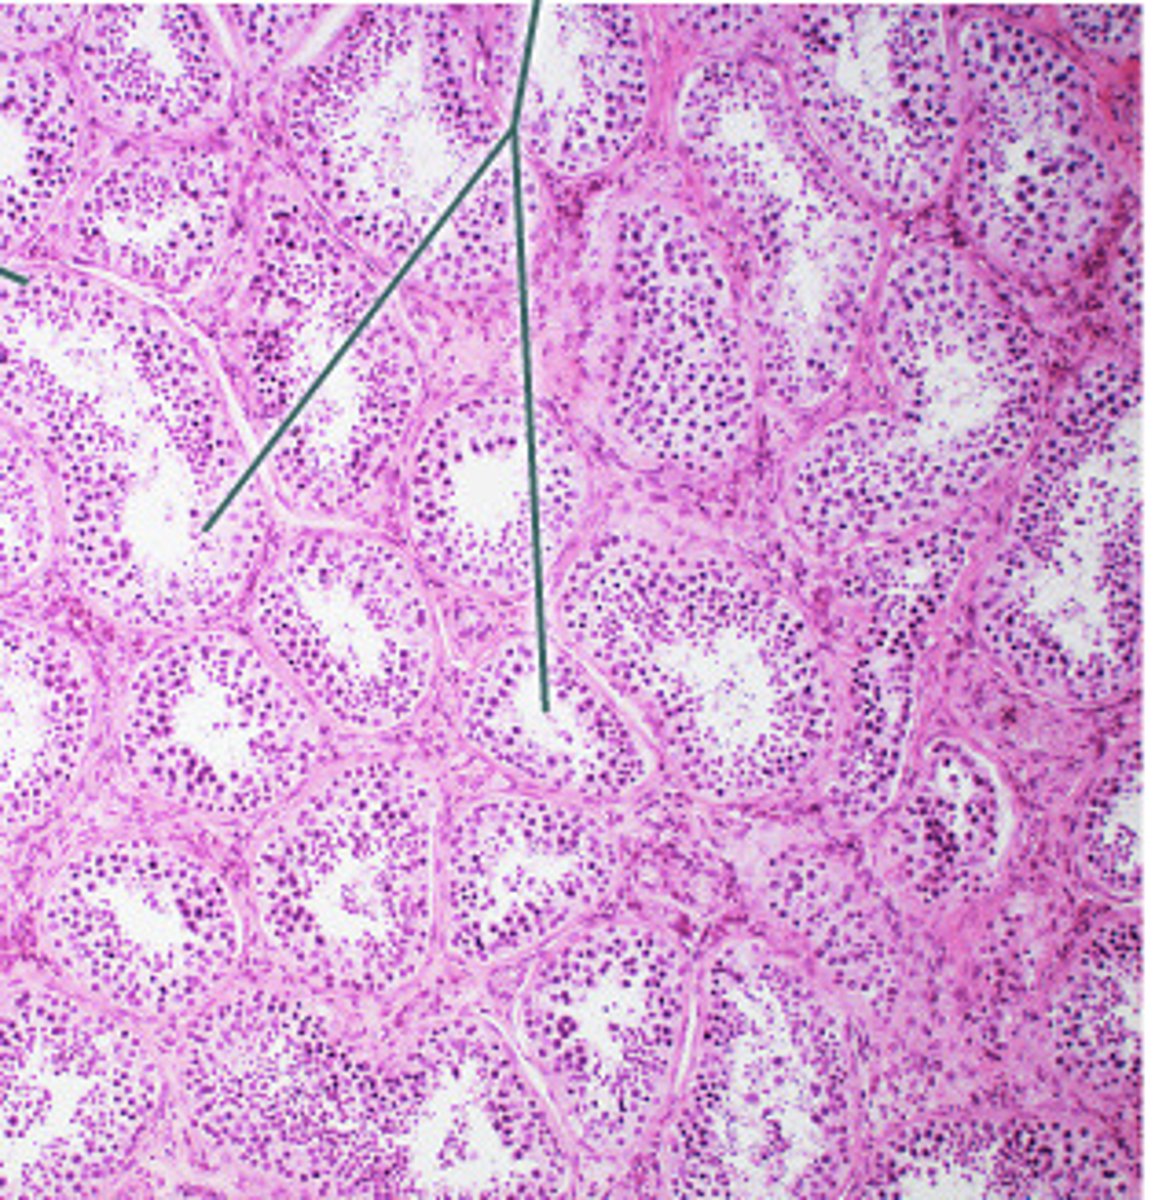

pancreas

what organ is this slide from

pancreatic islets of langerhans of pancreas

2

pancreatic acini (exocrine cells) of pancreas

1